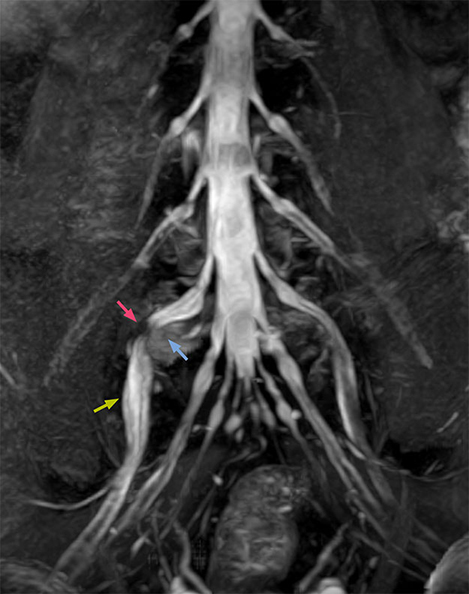

“In such case, we would then browse through axial T2-weighted MR images slice by slice and mentally reconstruct the actual situation based on both radiculography and MRI. Fortunately, NerveVIEW can now very well show nerve courses and presence of nerve compression or edema in one single image series.” “We have often seen NerveVIEW directly depict details of the nerve compression that were not observed by radiculography. Therefore, we think that with NerveVIEW we can reduce the number of invasive examinations, especially for some patients with lumbar plexus symptoms.”

“Before NerveVIEW, diagnosis by MRI alone was sometimes difficult, unless there was a strong suspicion based on clinical symptoms,” says Shoji Yabuki, MD, DMSc, Orthopedic surgeon at Fukushima Medical University School of Medicine. “This is why we routinely perform selective lumbosacral radiculography (nerve root block) and x-ray in such cases. However, radiculography can only depict nerves as far as the contrast agent reaches. When a nerve is distorted by compression, the contrast agent will not pass through this compressed area, preventing us from evaluating the full nerve compression.”

The key concept in MR neurography, Dr. Yabuki stresses, is the ability to directly visualize spinal nerves, versus inferring the presence of pathology indirectly. “Before NerveVIEW, we estimated compression of the nerve by looking for the presence or absence of fat signal on other MR images,” he says.

“For example, in sagittal images, when the presence of fat is observed in the intervertebral foramen, it suggests that there is a margin around the nerve. Similarly, the absence of fat indicates that the nerve is being compressed. So, we used to deduce nerve compression indirectly. With NerveVIEW, however, we can observe the condition of the nerves directly, regardless of the presence or absence of fat. We always prefer such direct observation of anatomy over having to make an inference about it.”

“NerveVIEW can clearly show nerve courses and presence of nerve compression. However, when multiple abnormalities are seen, it can still be hard to determine which nerve is causing the symptoms,” says Dr. Yabuki. “In our experience so far, we see abnormal findings on NerveVIEW in about 70% of elderly patients. As the pain is usually caused by only one nerve, we thus need to find the exact corresponding nerve.” “With a nerve root block, the patient's pain is improved by infiltration of local anesthesia directly around the nerve root considered to be responsible. Knowing such nerve root block findings prior to image interpretation, helps to easily recognize abnormal findings on NerveVIEW as well. In other words, without a priori knowledge, based on symptoms and/or nerve root block findings, we must be aware of the possibility of overdiagnosis.”